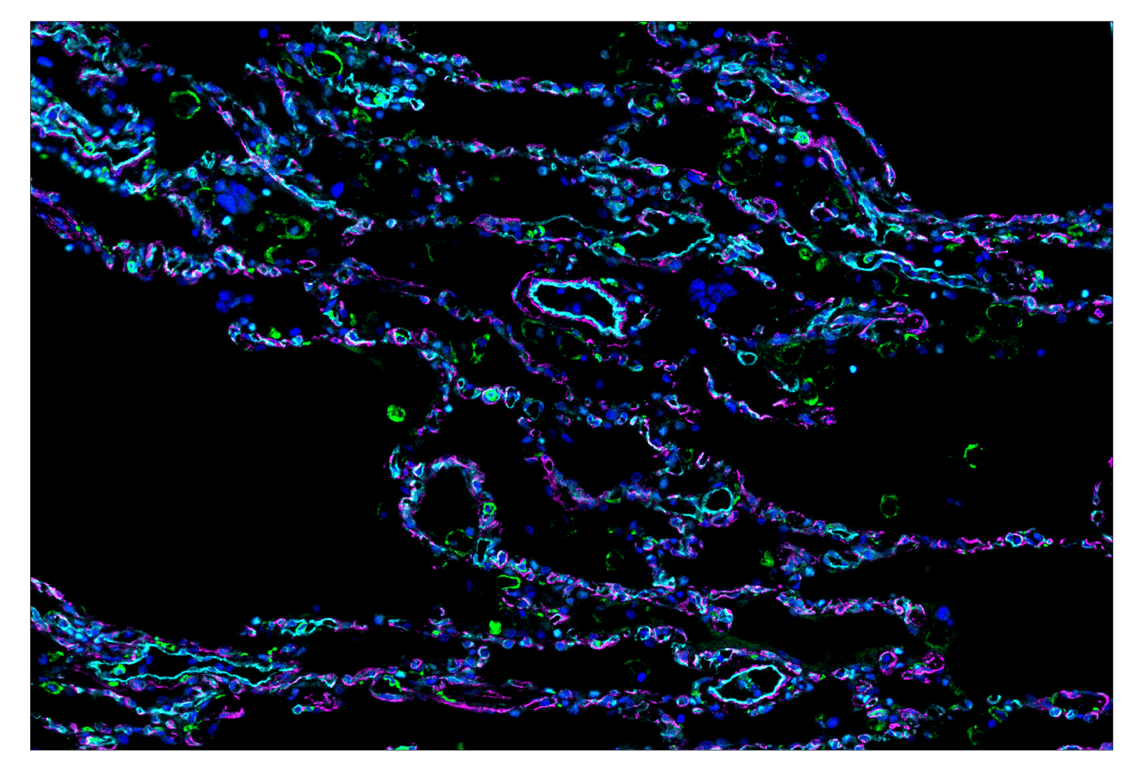

SignalStar™ multiplex immunohistochemical analysis of paraffin-embedded human gastrointenstinal stromal tumor using OX40L (D6K7R) & CO-0087-488 SignalStar™ Oligo-Antibody Pair #49516 (green), CD14 (D7A2T) & CO-0085-594 SignalStar™ Oligo-Antibody Pair #74041 (magenta), and CD141/Thrombomodulin (E7Y9P) & CO-0088-647 SignalStar™ Oligo-Antibody Pair #20811 (red). All fluorophores have been assigned a pseudocolor, as indicated. Staining was performed on the BOND RX autostainer by Leica Biosystems.

Immunohistochemistry Image 1: CD141/Thrombomodulin (E7Y9P) & CO-0088-647 SignalStar<sup>™</sup> Oligo-Antibody Pair